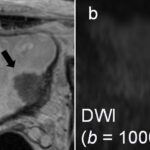

This sign is found in case of bladder cancer. It provides information on the degree of microinvasion into the muscularis propria. When absent, the likehood of progression is higher. Article: Usefulness of the inchworm sign on DWI for predicting pT1 bladder cancer...